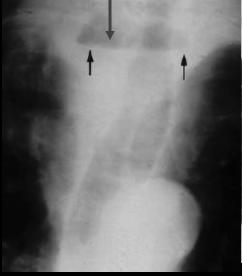

. -- --Images

radiologiques du diverticule epibronchique sont : Opacite

hydrique du mediastin sur le cliche pulmonaire sans

preparation de face et de profile . Image en ombre annulaire

sur cliche TOGD de face , image arrondies remplies par la

baryte avec le col du diverticule large et elle ne se vident

pas

Image arrondie en

niveau du diverticule epibronchique . Elle nese

vident pas |

Le plus souvent sont multiple et image en ombre

annulaire sur le cliche de face . |